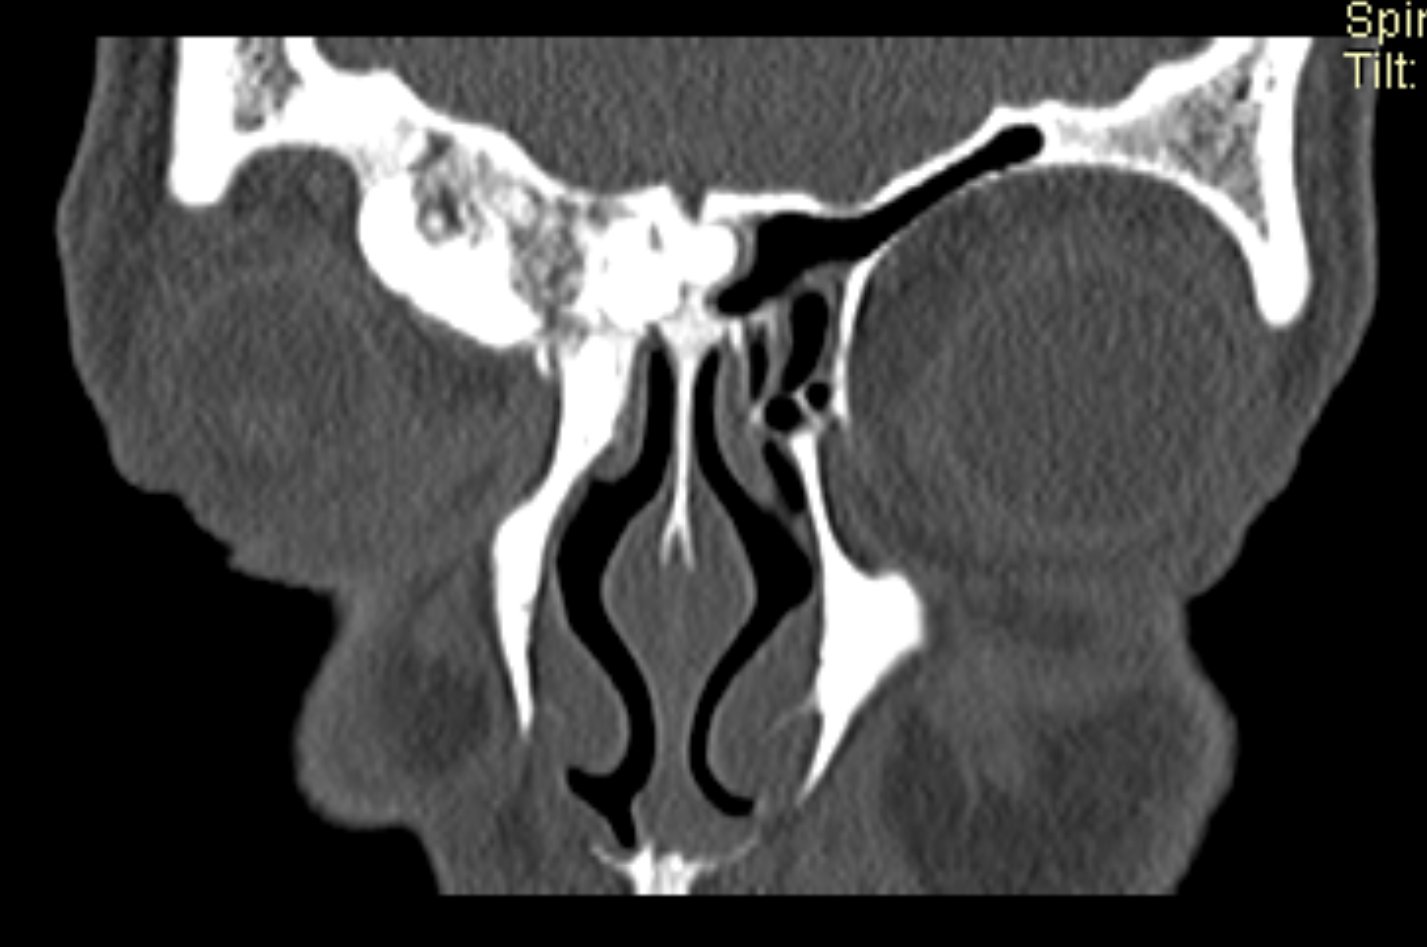

Examenul clinic ORL și examenele imagistice complementare (CT, RMN sinusuri paranazale) pun în evidență o formațiune tumorală osteogenică a sinusului frontal drept, protruzivă în unghiul supero-intern al orbitei, extinsă medial către sinusul frontal stâng.

- Se expune formațiunea tumorală osteomatoasă care ocupă în totalitate cavitatea sinusală frontală dreaptă, se extinde către sinusul frontal controlateral și către orbita dreaptă, creând presiune pe atmosfera celulo-grasoasă periorbitară la nivelul unghiului supero-intern OD. Formațiunea este intens aderentă la nivelul peretelui sinusal postero-superior. Aceasta prezintă două zone de consistență diferită.